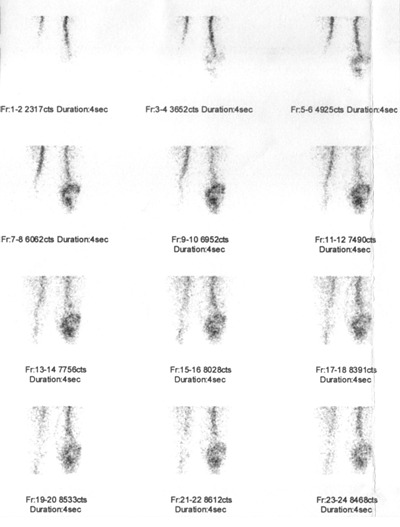

Pro podezření na uvolňování totální endoprotézy kolenního kloubu byl nemocný odeslán na naši kliniku ke scintigrafii skeletu. Na dvoudetektorové tomografické kameře E.CAM firmy Siemens byla provedena třífázová scintigrafie po i.v. aplikaci bolu (v malém objemu) 700 MBq

99mTc-oxidronátu (přípravek TechneScan HDP firmy Mallinckrodt

Medical). V první i druhé fázi scintigrafie byla zvýšená depozice radiofarmaka v oblasti celého pravého kolenního kloubu kolem femorální i tibiální komponenty TEP. Ve druhé fázi je zvýšena depozice radioindikátoru v oblasti mediálního kondylu pravé

tibie. Tento nález svědčí pro zvýšenou perfuzi (prokrvení) v oblasti levého kolena a v oblasti mediálního kondylu pravé tibie

(obr.1, 2).

/ Obr. č. 1: Třífázová scintigrafie skeletu – 1. fáze (perfuze). Scintigrafie kolenních kloubů a přilehlých částí kostí stehenních a kostí bérců po aplikaci radiofarmaka

99mTc-oxidronátu v přední projekci /